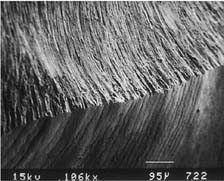

Table 7-3 MARGINS PRODUCED BY VARIOUS TYPES OF BURS

| Bur appearance | Low magnification of the prepared margin | High magnification of the prepared margin |

|---|---|---|

| CHAMFERS | ||

| Chamfer carbide (high speed) | ||

![]() |

| Finishing carbide (high speed) | ||

| Finishing carbide (low speed) | ||

| Chamfer diamond coarse (high speed) | ||

| Fine diamond (high speed) | ||

| Chamfer diamond fine (low speed) | ||

| SHOULDERS | ||

| Cross-cut fissure (high speed) | ||

| Cross-cut fissure (high speed) and hoe | ||

| Cross-cut fissure carbide (high speed) | ||

| Flat-end coarse diamond (high speed) | ||

| Flat-end coarse diamond (high speed) and hoe | ||

| Fine grit diamond (high speed) | ||

| Fine grit diamond (low speed) | ||

Courtesy of Dr. H. Lin.